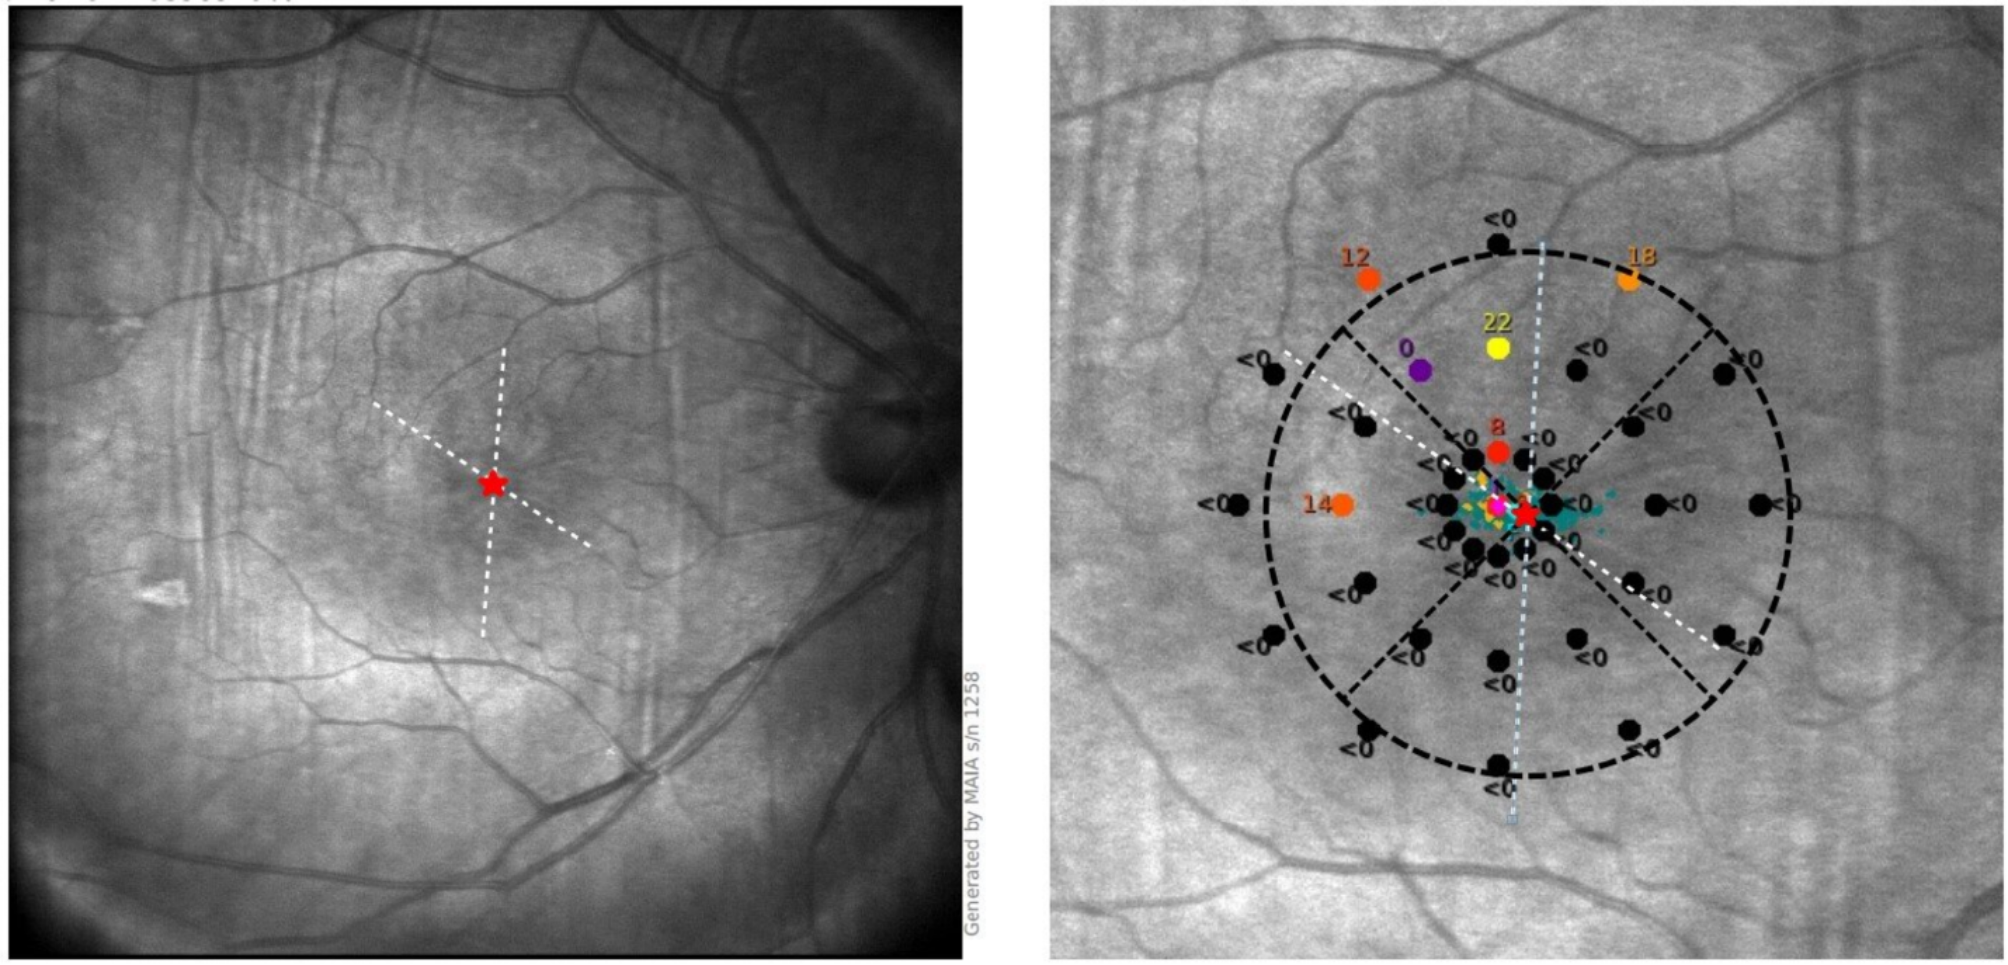

The image of MAIA in eye with PRL located inside dark areas.